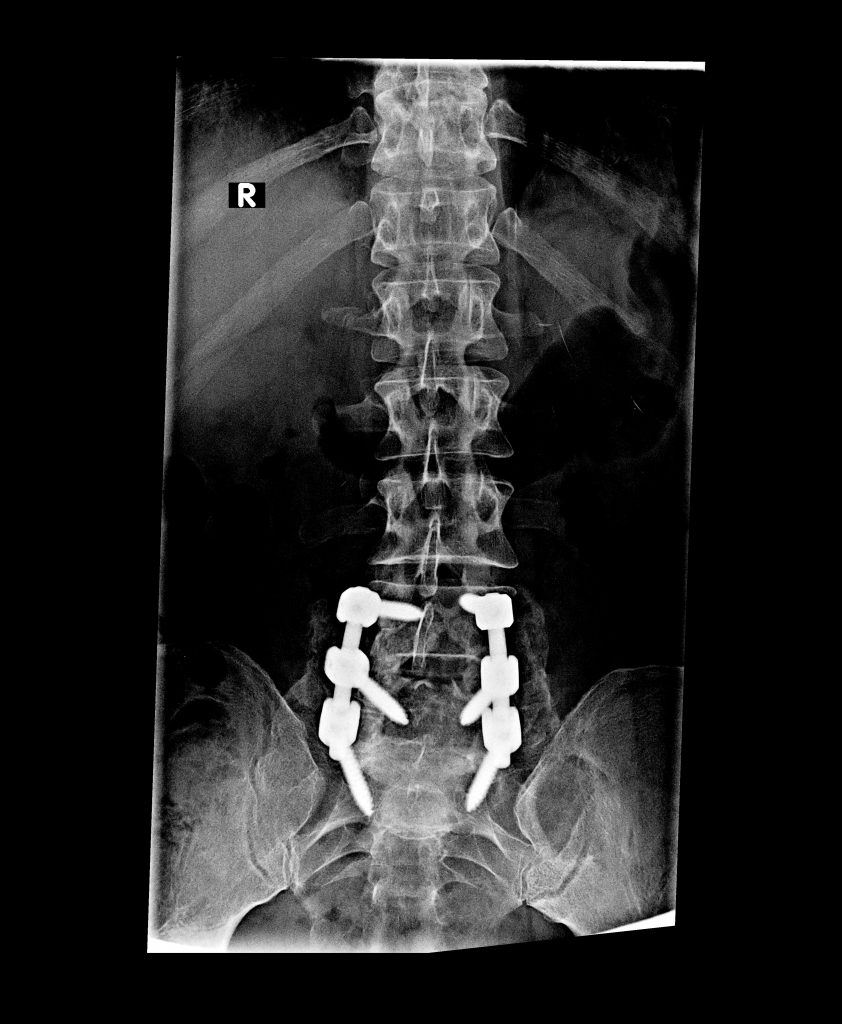

Spinal Fusion Surgery

For multiple level disc herniation, I had a discectomy performed by Dr. Rawlins in 2012. After 8 healthy years, the eventuality of having a larger surgery came about. There was no doubt that I would seek to have treatment by Dr. Rawlins and the great team at HSS. Dr. Rawlins is professional, friendly and caring. His team is responsive and help guide me through the whole process with ease, considering travel arrangements I required.